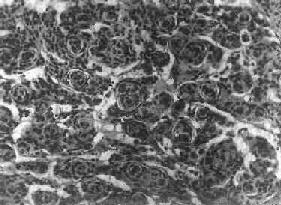

镜下,细胞大小形态一致,呈梭形或胡萝卜形,胞核圆或椭圆,染色质呈细颗粒状,核膜清楚,有核仁。细胞胞浆丰富,突起明显。细胞的排列有二种特征,一是环绕空腔排列成腺管状,形态上与室管膜腔相似,称为菊形团形成,另一是环绕血管形成假菊形团结构,细胞有细长的胞浆突起与血管壁相连(图16-25)。细胞中有神经胶质纤维,以PTAH染色在个别细胞的腔面或胞核旁可见纤毛体,后者与纤毛运动有关,是室管膜细胞的特征性结构。此外,有时还可形成乳头状结构。发生在脊髓圆锥和终丝的肿,乳头状结构轴心中的结缔组织往往富含粘液。

细胞为圆形或卵圆形,核染色质丰富,胞浆少,可见有细长的胞浆突起与血管相连,呈放射关,形成假菊形团